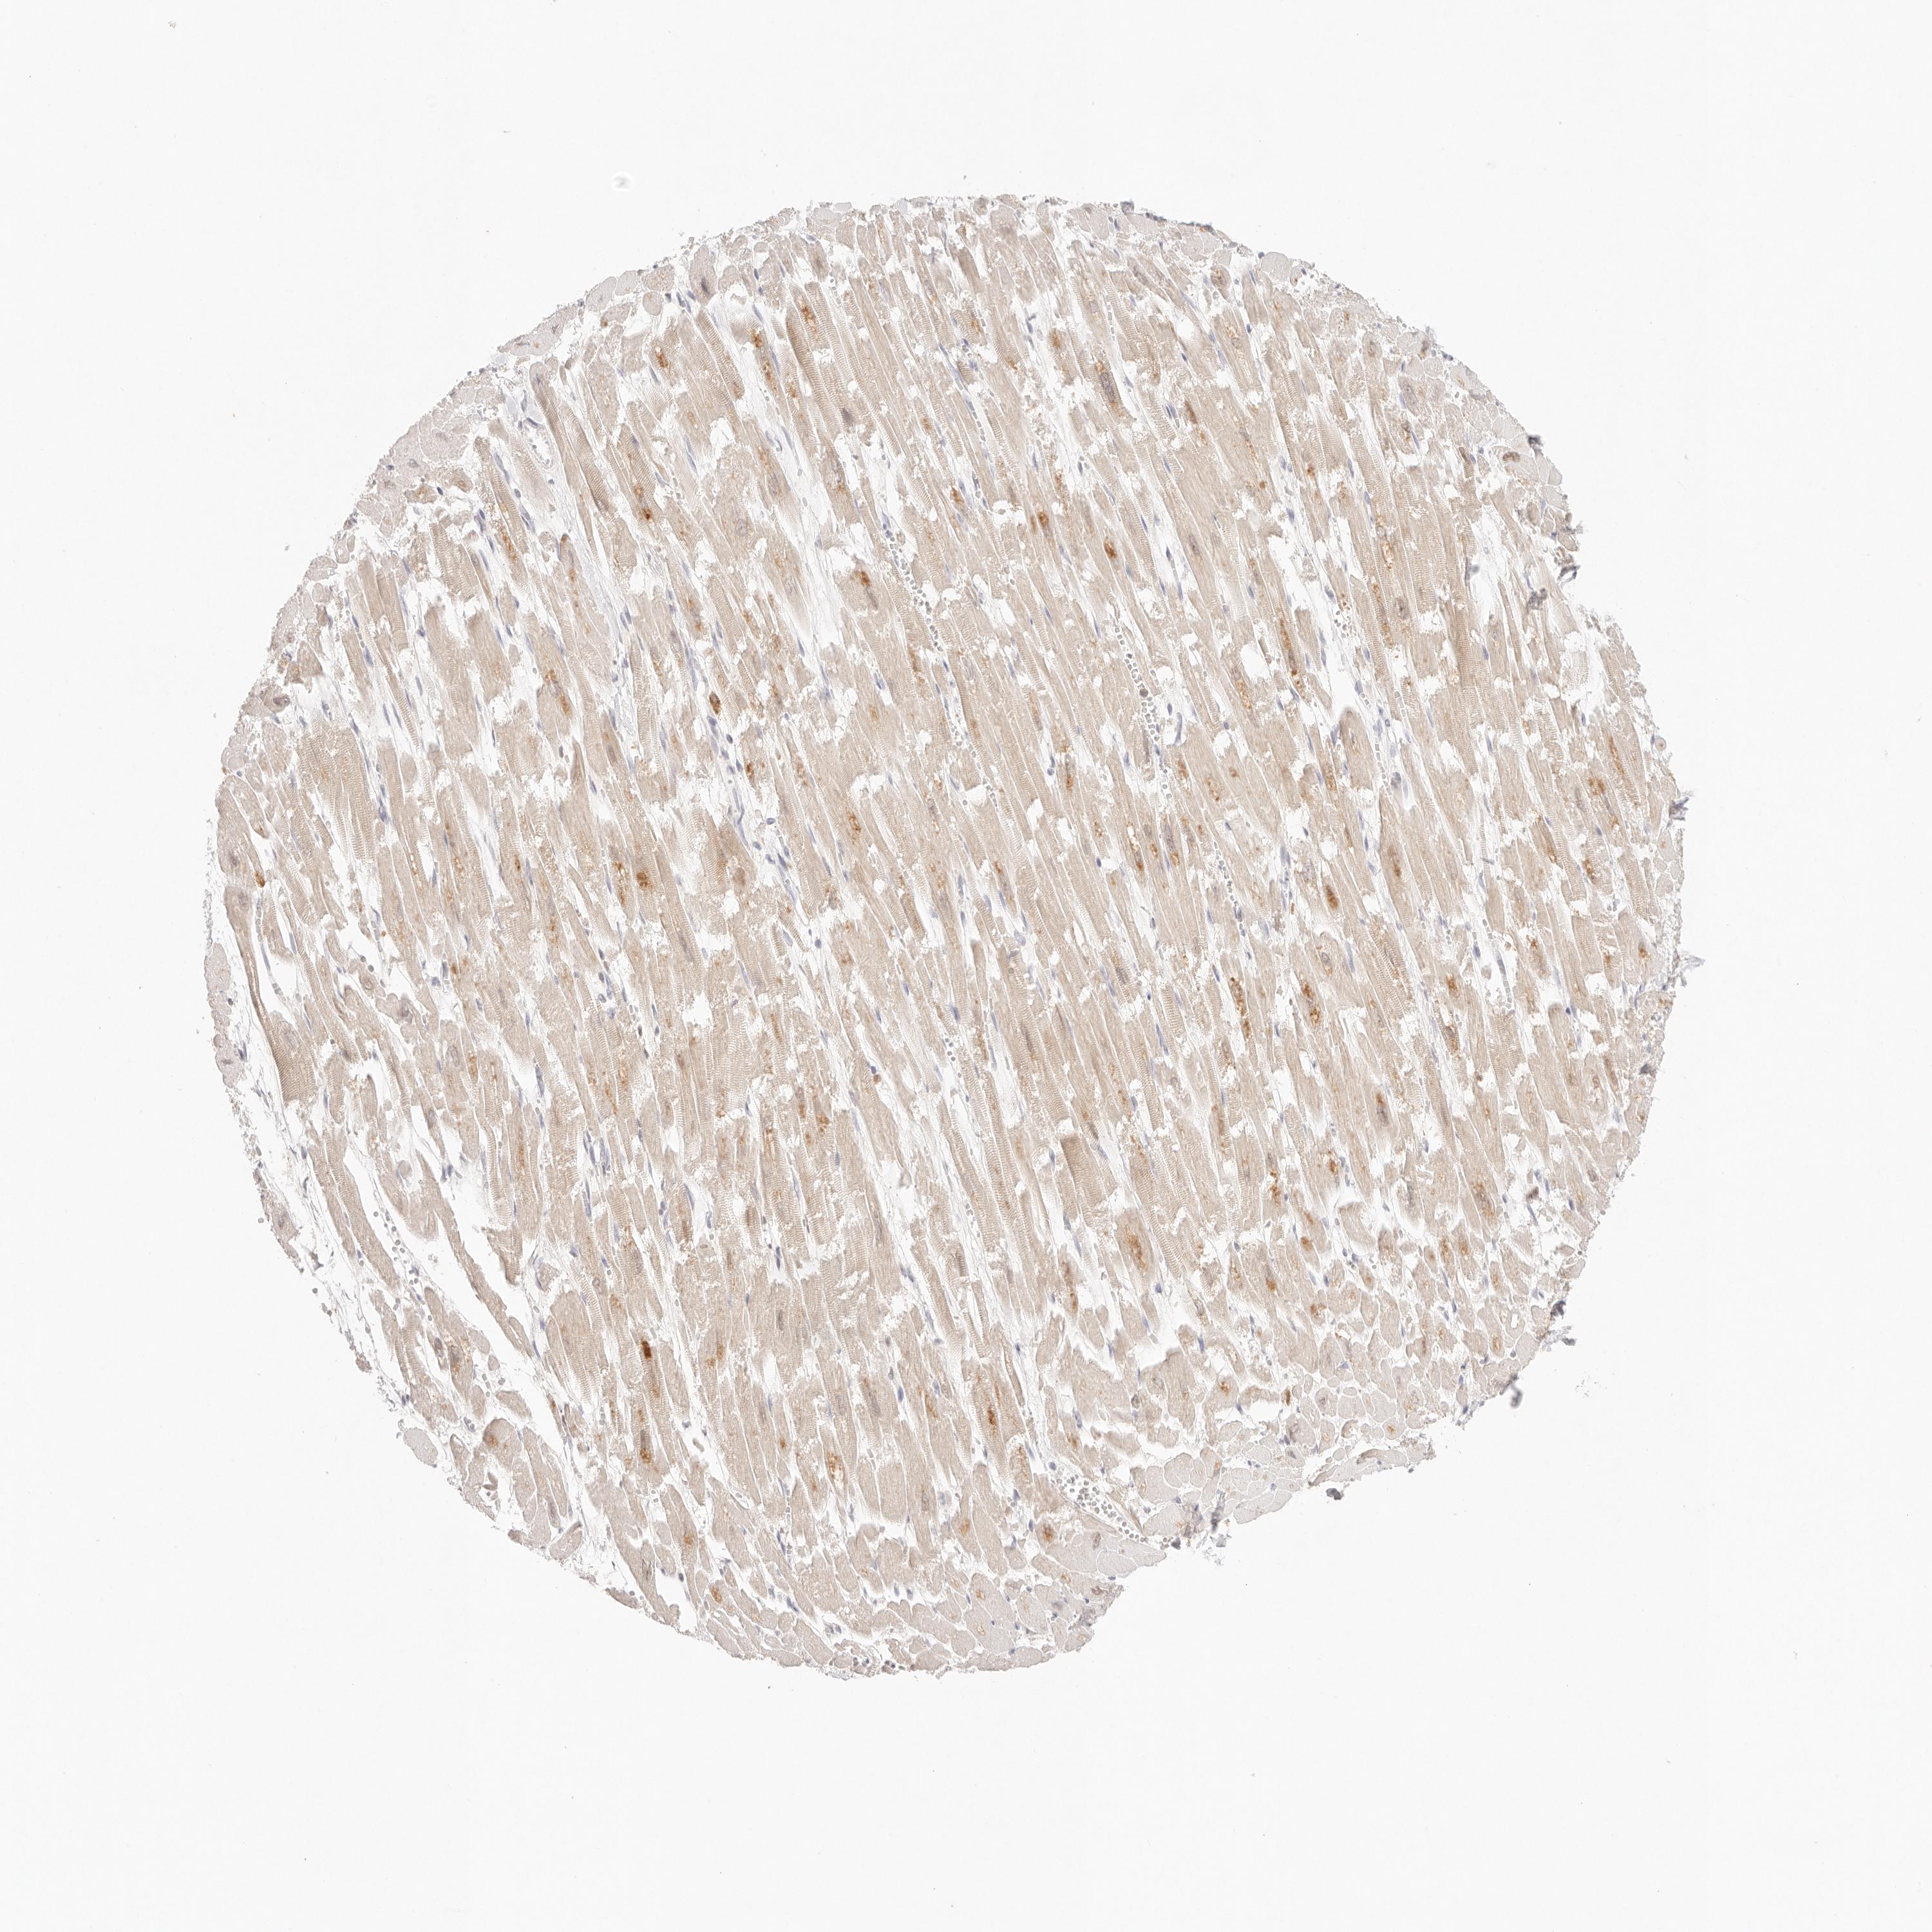

HEART MUSCLE - Antibody stainingi

Antibody staining in the annotated cell types in the current human tissue is reported as not detected, low, medium, or high, based on conventional immunohistochemistry profiling in selected tissues. This score is based on the combination of the staining intensity and fraction of stained cells.

Each image is clickable and will lead to virtual microscopy that enables deeper exploration of all samples and also displays staining intensity scores, fraction scores and subcellular localization as well as patient and tissue information for each sample.

Antibody HPA022829Antibody HPA028761

Cardiomyocytes MediumLow